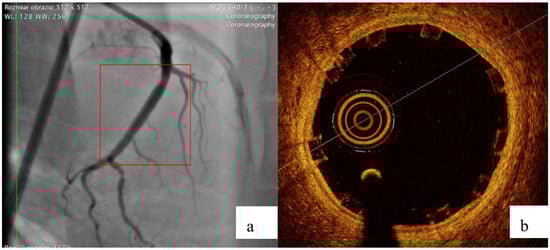

2.4. Biological Reponse in the Large Model of Coronary In-Stent Restenosis

The part of study was approved by local bioethical committee for animal experimentation (Medical University of Silesia, Katowice, Poland). To validate the mathematical and mechanical modeling tests described above, three PLGA/PLLA blend polymer stents (3.0 in diameter, 15.0 mm length) were implanted with standard percutaneous techniques in three coronary arteries of domestic swine with 110% overstretch. Following coronary angiography, intravascular optical coherence tomography (OCT) was utilized before and after the stent implantation to size the vessel. Stents were deployed after reaching body temperature with slow in mid portion of one of the three coronary arteries with stepwise inflation—2 atmospheres per 5 s. Following post implantation coronary angiography and OCT were performed. Animals were scheduled for 28-day follow-up with coronary angiography and OCT.

3.2. Biological Response

All three stents were implanted successfully. In coronary angiography stents showed enough radial force to support overstretched vessel (Figure 13). The OCT has shown good stent apposition and the analysis has shown lumen enlargement post implantation 24% as shown in Figure 13c. At 28-day follow-up, all stents were covered with neointima, and struts embedded. Interestingly the signs of material hydrolysis were observed thus proving the polymer amorphic properties (Figure 14).

Figure 13.

Acute outcome after PLGA/PLLA blend polymer stent implantation in coronary angiography (a) and optical coherence tomography (b). Lumen area increase before and after implantation (c). Geometrical view of vessel after stent implantation (d).